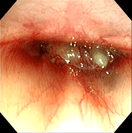

‣当院での症例紹介

鼻腔内腫瘍(犬)

鼻腔内腫瘍(猫)